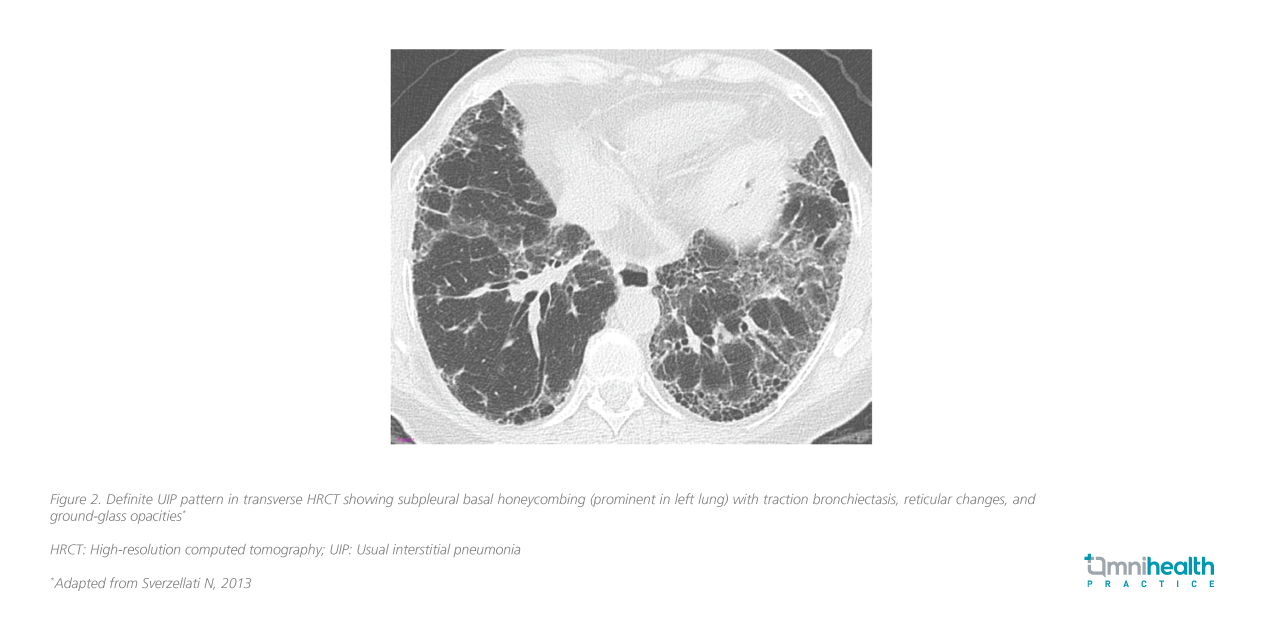

Fibrosis and inflammation are central to ILD pathogenesis, with progressive lung scarring impairing gas exchange, leading to respiratory failure in advanced cases.1,2 Usual interstitial pneumonia (UIP) is a key high-resolution computed tomography (HRCT) pattern characteristic of IPF and some advanced fibrotic ILDs (e.g., CTD-ILD, chronic HP, asbestosis) (figure 2).3,6 In the right clinical context, HRCT alone may suffice for an IPF diagnosis without biopsy.3

HRCT plays a critical role in identifying ILD progression.3,6 While fibrosis may be subtle in early stages, advanced disease is marked by extensive honeycombing and reticulation patterns.6 She emphasized that prognosis is highly dependent on disease status at presentation, with earlier diagnosis and treatment correlating with better long-term outcomes.10 Beyond traditional lung function measures, serum biomarkers such as Krebs von den Lungen-6 (KL-6) and surfactant protein D (SP-D) have gained recognition for their role in predicting disease progression and treatment response.11 Their growing clinical utility highlights the need for further research and standardized integration into ILD management.6